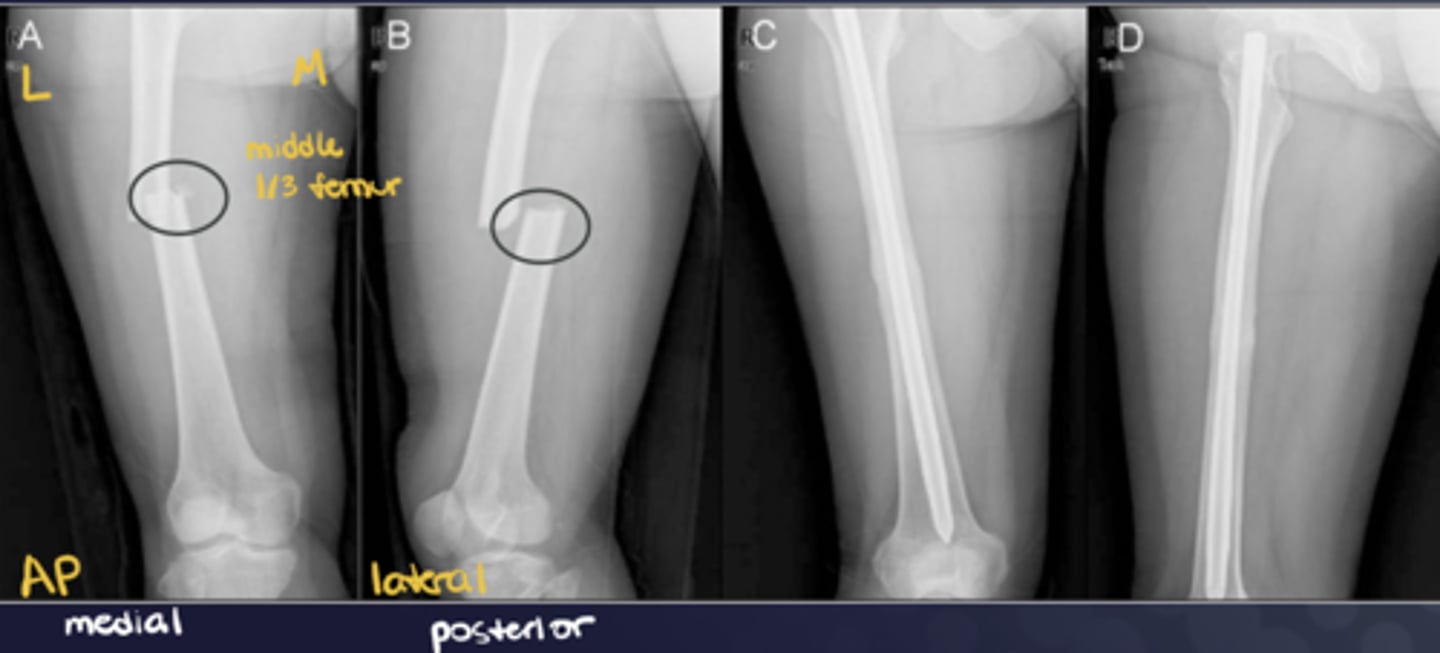

What does good position, good alignment look like vs. displaced with deviated alignment?

See image.

Name displacement based on the ________ fracture end in anatomical position

DISTAL!! -- i.e., "displaced medial, posterior, and overriding"

Name deviation based on the ________ bone angle in the ________ direction

DISTAL!! -- i.e., "deviated medial and anterior"